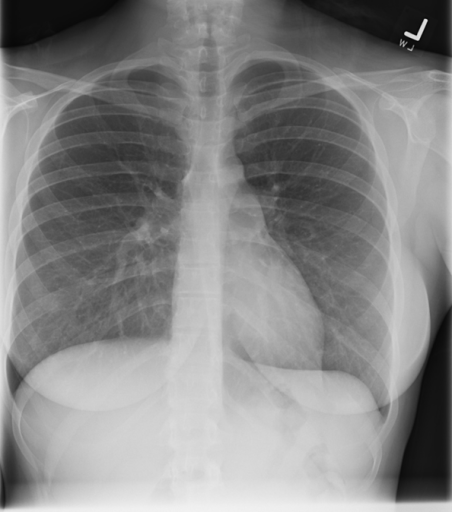

PA/lateral projection is the standard used for most patients who are ambulatory and able to stand. In this view, the mediastinum should have a normal width and a good inspiratory effort should results in full diaphragm expansion.

PA Projection – Normal Mediastinum and Good Inspiratory Effort